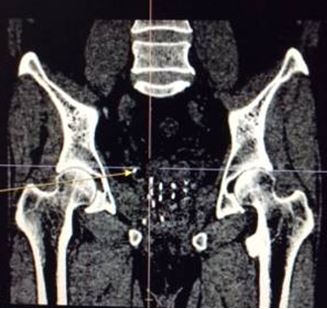

• Chụp XQ khung chậu thẳng: vị trí kim được cắm tốt

Về lâm sàng: Bệnh nhân có tụ máu nhẹ tầng sinh môn; ăn ngủ, sinh hoạt tốt; không sốt, không đái buốt, không đái rắt.

Theo dõi sau điều trị 1 tháng: BN sinh hoạt bình thường, tiểu tiện tốt, chức năng sinh dục tốt, xét nghiệm PSA 3,4 ng/ml.

Sau điều trị 7 tháng (12/2015):

- Lâm sàng: bệnh nhân thể trạng tốt, đi tiểu bình thường, chức năng sinh dục không giảm so với trước điều trị, không đi ngoài ra máu

- Chụp MRI: Không thấy khối bất thường trên hình ảnh MRI tiểu khung

- Xét nghiệm PSA toàn phần tiếp tục giảm xuống còn 0,91 ng/ml, PSA tự do 0,15 ng/ml.

So sánh trước và sau điều trị:

Trước điều trị: khối u tuyến tiền liệt ranh giới rõ, bắt thuốc mạnh, kích thước 15 mm, chưa xâm lấn vỏ bao và túi tinh 2 bên; PSA = 28,5 ng/ml

Sau điều trị 7 tháng: không còn u trên cộng hưởng từ, nồng độ PSA về bình thường, bệnh nhân hết đi tiểu khó, thể trạng tốt; PSA giảm xuống rất nhiều còn 0,91 ng/ml.